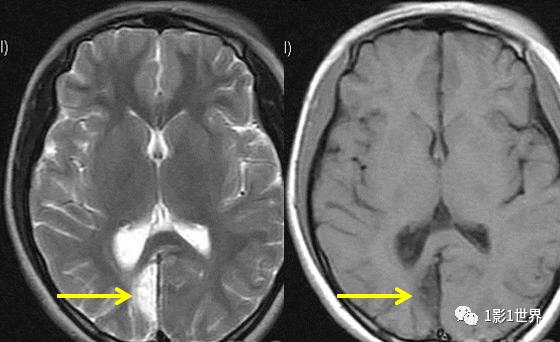

慢性期: • 形态:表现为低密度的囊腔,形态不规则,边界清晰锐利。 • 密度:与脑脊液密度相近(CT值接近0-10 HU)。 • 周围:常伴有局限性脑萎缩,如邻近的脑沟增深、脑室扩大。 • 占位效应:**无**或极轻微,甚至因局部萎缩而有“负占位”效应。 |

MRI表现非常具有特征性 • T1WI:呈极低信号(与脑脊液信号一致)。 • T2WI/FLAIR:呈极高信号(FLAIR上信号很高,与周围脑脊液信号差异大,这是与新鲜梗死的区别)。 • DWI/ADC:呈等信号(因为水分子可以自由弥散,没有受限)。 • GRE/SWI:常可见含铁血黄素沉积导致的低信号环或斑片状低信号(代表陈旧性出血)。 • 周围:可见明显的局部脑萎缩和胶质增生(T2WI/FLAIR上呈高信号的边缘环)。 |

- 脑软化灶 vs 蛛网膜囊肿: 两者在CT和T1/T2上信号相似,但蛛网膜囊肿边界更光滑,常位于脑沟/脑裂处,不伴有周围胶质增生和明显的局部脑萎缩,FLAIR上蛛网膜囊肿内信号与脑脊液一致(被抑制),而软化灶的囊液在FLAIR上仍为高信号。